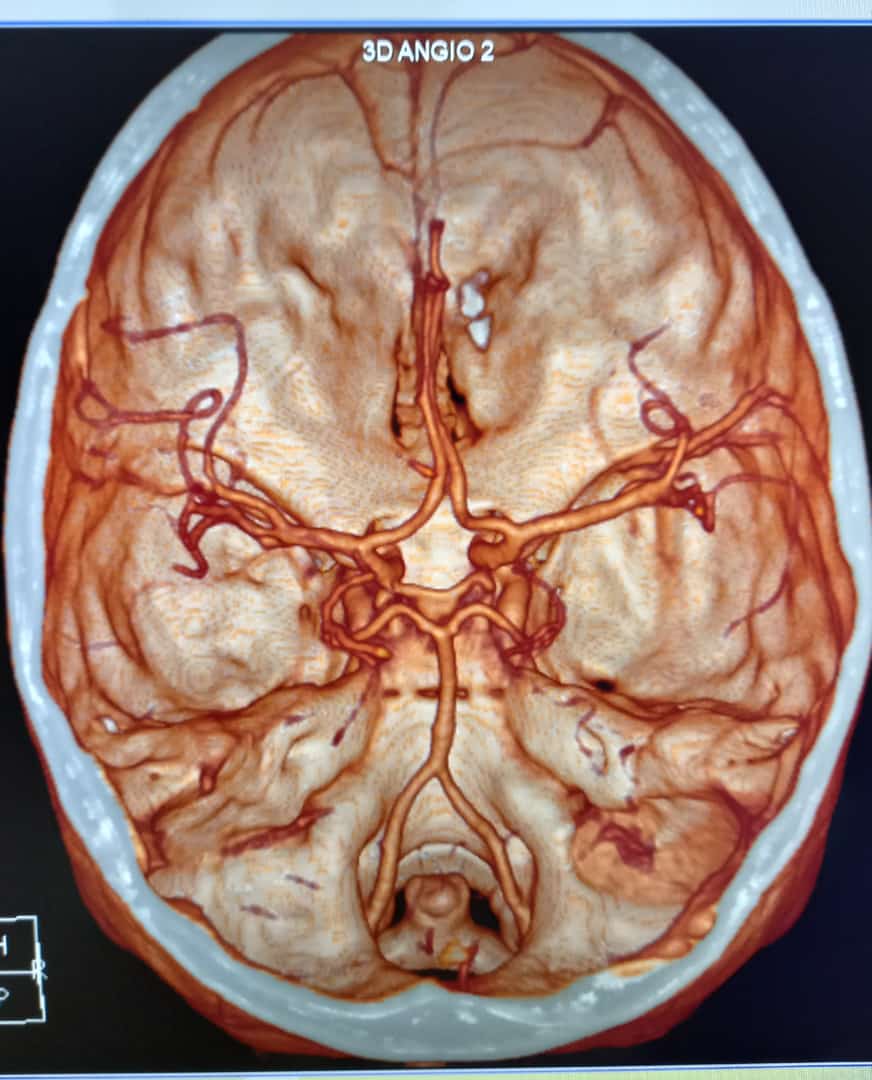

El Angio 3D es un procedimiento diagnóstico de última generación que utiliza equipos especializados como tomógrafos computarizados de alta tecnología para obtener imágenes tridimensionales detalladas de los vasos sanguíneos en diversas partes del cuerpo, especialmente en el cerebro.

Durante el Angio 3D, el paciente es colocado dentro del tomógrafo, que está equipado con computadoras potentes que procesan múltiples imágenes obtenidas desde diferentes ángulos. Estas imágenes se combinan para crear una representación tridimensional precisa de los vasos sanguíneos y las estructuras circundantes. Esta técnica permite una visualización detallada y una evaluación minuciosa de cualquier anomalía vascular.

- Precisión Diagnóstica: Las imágenes tridimensionales proporcionadas por el Angio 3D permiten una evaluación detallada y precisa de las condiciones vasculares, ayudando a los médicos a planificar tratamientos adecuados.